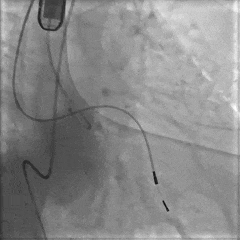

6mm外周球囊扩张狭窄处

造影定位球囊位置

再次扩张狭窄段

扩张后造影

大鞘置入至降主动脉